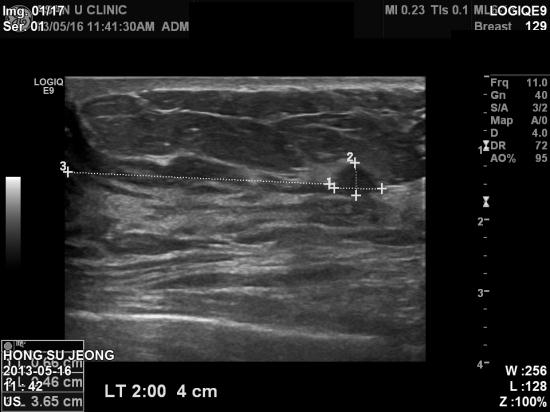

본원 초음파 검사상 좌측 유방 2시방향 유두에서 4cm 떨어진곳에서 결절소견 및,